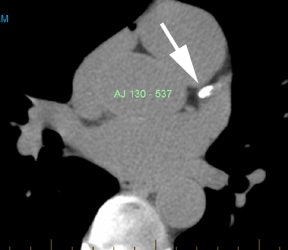

Coronary artery calcification: The patient below has a large calcification in their proximal LAD. Their total calcium score was 537. |